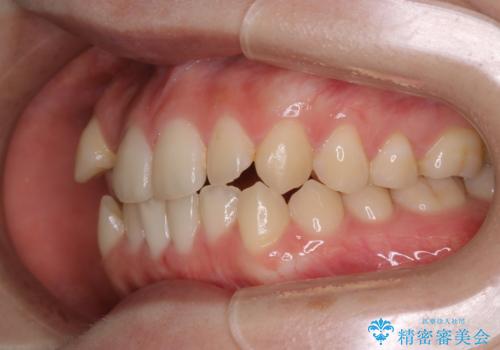

八重歯とクロスバイト:インビザライン治療

- 八重歯が気になるとの事でご相談にいらした方です。

インビザラインで綺麗に並べました。

気になっていた八重歯が綺麗になって大変喜んでいただけました。